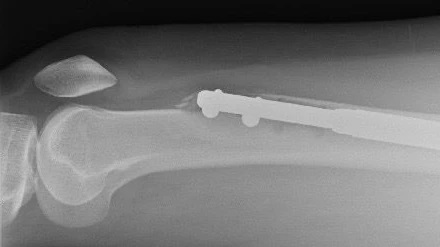

Con este procedimiento, sentir cierto dolor es esperable. Durante la operación, los huesos de las piernas se rompen en dos y una varilla de metal se posiciona adentro.

Las varillas de metal se van expandiendo gradualmente para aumentar su longitud y separar las dos mitades del hueso. El objetivo del procedimiento es aumentar la estatura del paciente. Los huesos rotos deberían volver a unirse gradualmente y llenar así el espacio que se creó entre ellos.

Esto es lo que hace que el clavo se alargue y las piernas crezcan. Pero dos semanas después, dice, ocurrió el desastre. “Tenía mucho dolor en la pierna izquierda. Una noche, mientras me movía en la cama, oí un crujido parecido al de un [chocolate] Kit Kat, seguido de un dolor intenso”.

Elaine fue a hacerse una tomografía y terminó confirmando sus miedos. El clavo de la pierna izquierda le había atravesado el fémur, el hueso más fuerte del cuerpo humano. Estaba angustiada, pero dice que el doctor Guichet la calmó.

“El doctor Guichet me dijo que el clavo se había roto mientras lo sacaba”, explica. “Tenía un clavo de otro paciente que pudo insertar”.